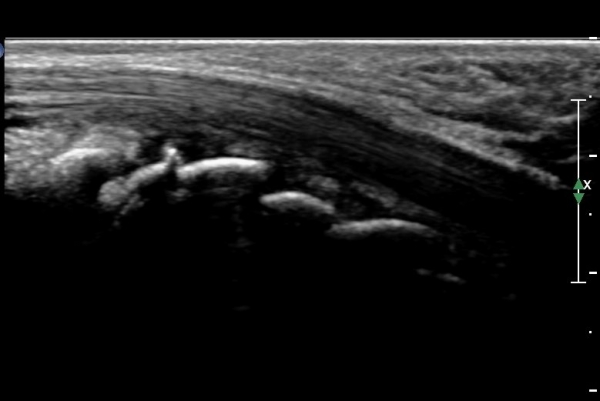

ÃÊÀ½ÆÄ°Ë»ç : ¼Õ¸ñ ¹èÃø Á¾´Ü¸é°Ë»ç¿¡¼­ ¼ö±Ù°üÀý³» ¼ö¾×Àú·ù°¡ °üÂûµÊ(»çÁø 1).